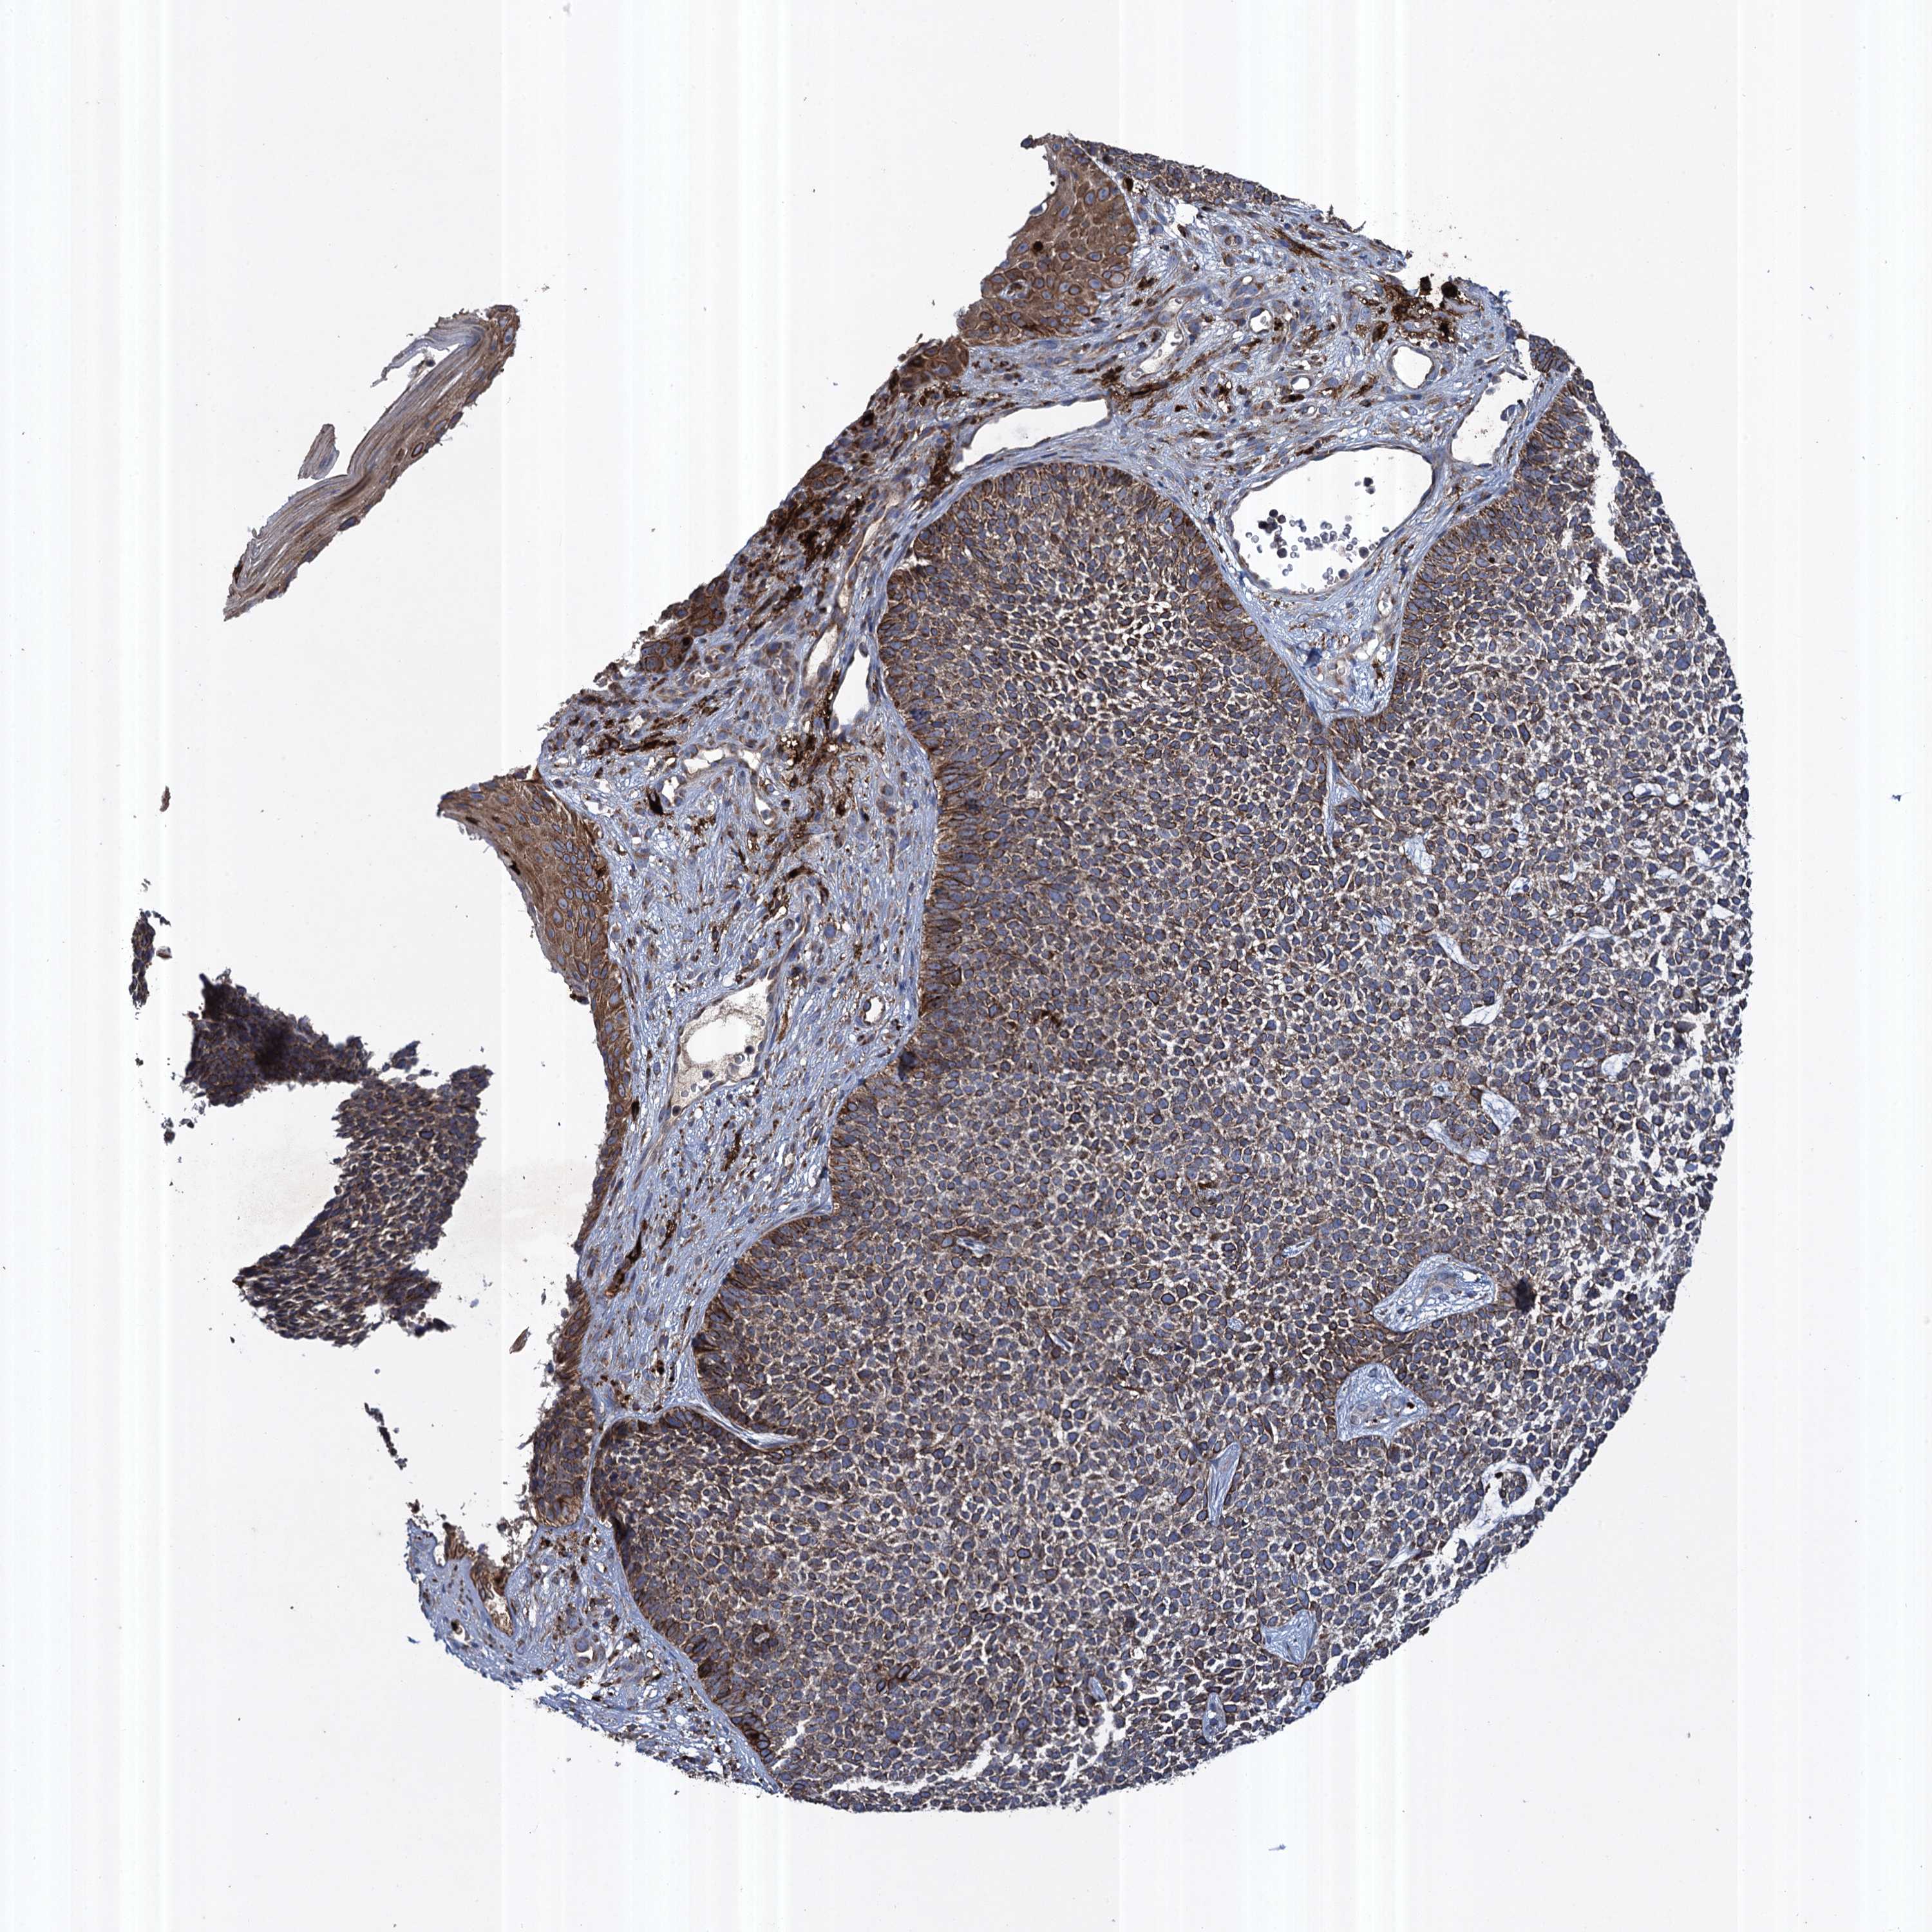

SKIN CANCER - Protein expressioni

A mouse-over function shows sample information and annotation data. Click on an image to view it in a full screen mode. Samples can be filtered based on level of antibody staining by selecting one or several of the following categories: high, medium, low and not detected. The assay and annotation is described here.

Antibody staining in the annotated cell types in the current human tissue is reported as not detected, low, medium, or high, based on conventional immunohistochemistry profiling in selected tissues. This score is based on the combination of the staining intensity and fraction of stained cells.

Each image is clickable and will lead to virtual microscopy that enables deeper exploration of all samples and also displays staining intensity scores, fraction scores and subcellular localization as well as patient and tissue information for each sample.

Antibody HPA041174

Basal cell carcinoma